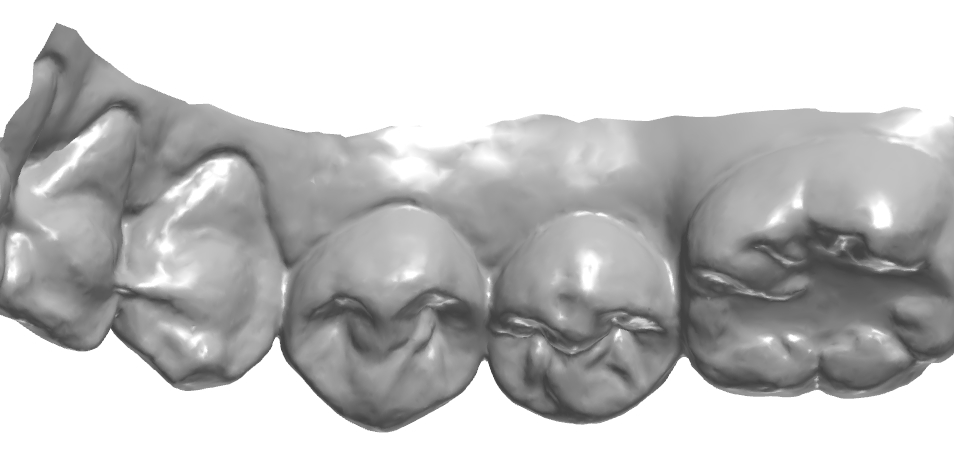

설측 엠브레져 체크.

설측 교두 체크.

설면에서의 풍융도 체크.